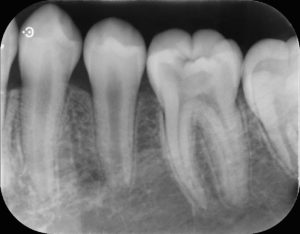

左下第一大臼歯にう窩がみられたため、レントゲン写真で虫歯の範囲を確認すると歯髄に近接した透過像をみとめた。症状はまったくなく、若年者でもあったため歯髄の保存を試みた。虫歯の除去中に容易に露髄し、歯冠部歯髄は一部壊死していたため歯頚部にて断髄を行い、MTAセメントにて歯髄保存を試みた。一定期間経過観察の後、症状の無いことを確認した後、ダイレクトボンディングにて歯冠修復を行った。

術前のレントゲン写真を見てもわかるように明らかにう蝕が歯の神経に到達している大きな虫歯なので、治療としては神経を取り除き、銀歯などの被せ物を作るのが一般的な治療となります。

ですが、若いうちに神経を取り除いてしまうと、その後歯の耐久性が弱くなってしまいます。すべての症例ではありませんが、このケースのように症状がないなどの条件を満たせば、MTAセメントにより保護することで神経の温存を行うこともできます。